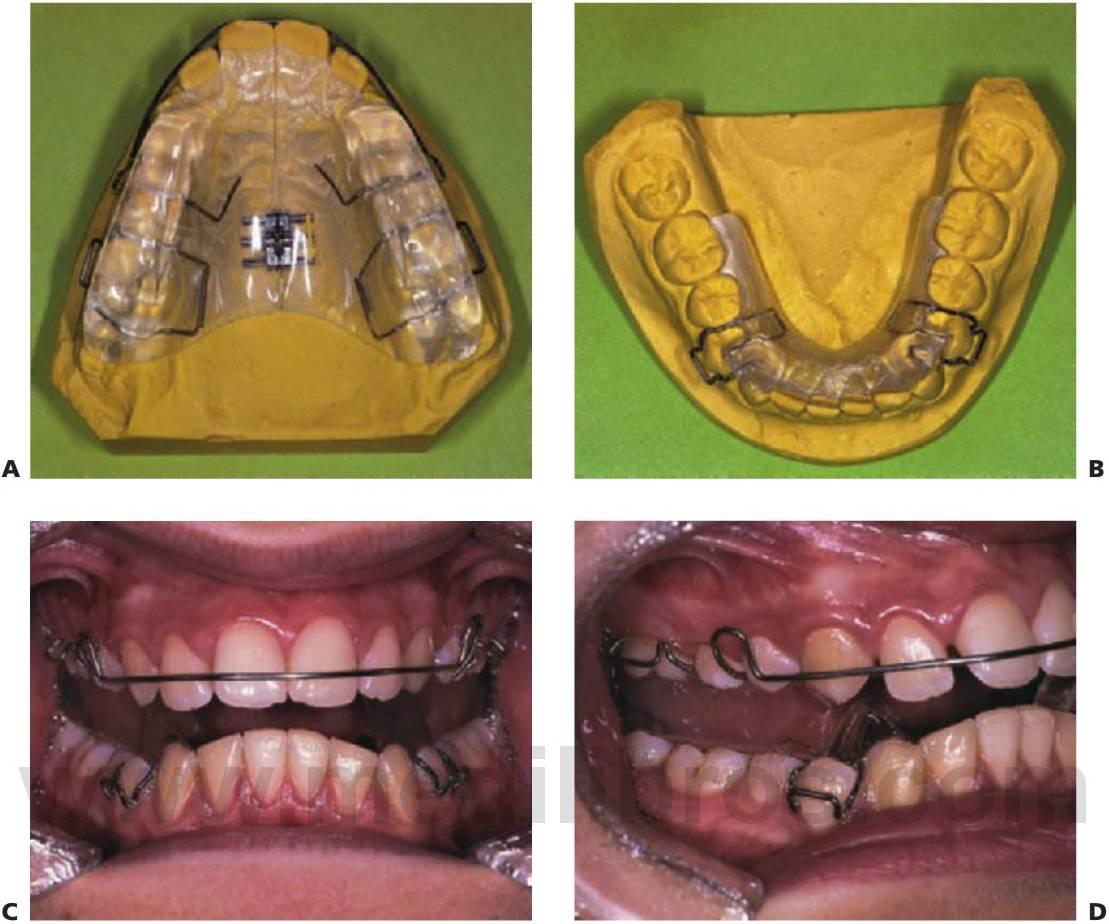

Aparato de bloques gemelos de Clark

El aparato de bloques gemelos es un aparato funcional de dos piezas. Los bloques superior e inferior están fabricados de acrílico y se unen en la zona de los premolares formando un ángulo de aproximadamente 70°, lo que resulta suficiente para mantener la postura avanzada mandibular. Un niño puede hablar, comer y vivir con el aparato puesto. Al tratarse del único aparato funcional a tiempo completo, se espera que su funcionamiento cause adaptaciones esqueléticas, dentales y neuromusculares rápidas.

El bloque gemelo superior puede alojar un tornillo de expansión, así como resortes, para realizar movimientos pequeños en un diente o dientes. Por ello, mientras se produce el reposicionamiento mandibular también se producen la expansión simultánea del maxilar y el alineamiento de pequeñas malposiciones de los dientes, lo que elimina la necesidad de la fase de tratamiento prefuncional y acorta el tiempo total de tratamiento.

El aparato de bloques gemelos ofrece flexibilidad de uso con aparatos fijos que pueden resultar necesarios para la terminación y el detalle en la segunda fase del establecimiento de la oclusión. De ahí que el tiempo de tratamiento total pueda ser aún más corto (fig. 11.20).

Secuencia del tratamiento (figs. 11.21, 11.22)

- Selección del caso y planificación del tratamiento.

- Preparar registros completos.

- Necesidad de retirar de forma progresiva cualquier tratamiento ortodóncico prefuncional relevante o la posibilidad de movimiento simultáneo de dientes en fase activa.

- Registro de mordida: avanzar la mandíbula a la posición de borde a borde para el registro de la mordida.

- Fase activa.

- Uso y seguimiento del aparato.

- Recorte del acrílico que permita la erupción selectiva de dientes para la corrección de la mordida abierta y la corrección molar sagital.

- Fase de apoyo.

- La placa de mordida acrílica modificada mantiene la mandíbula hacia delante.

- Acabado y detalle con aparatos fijos.